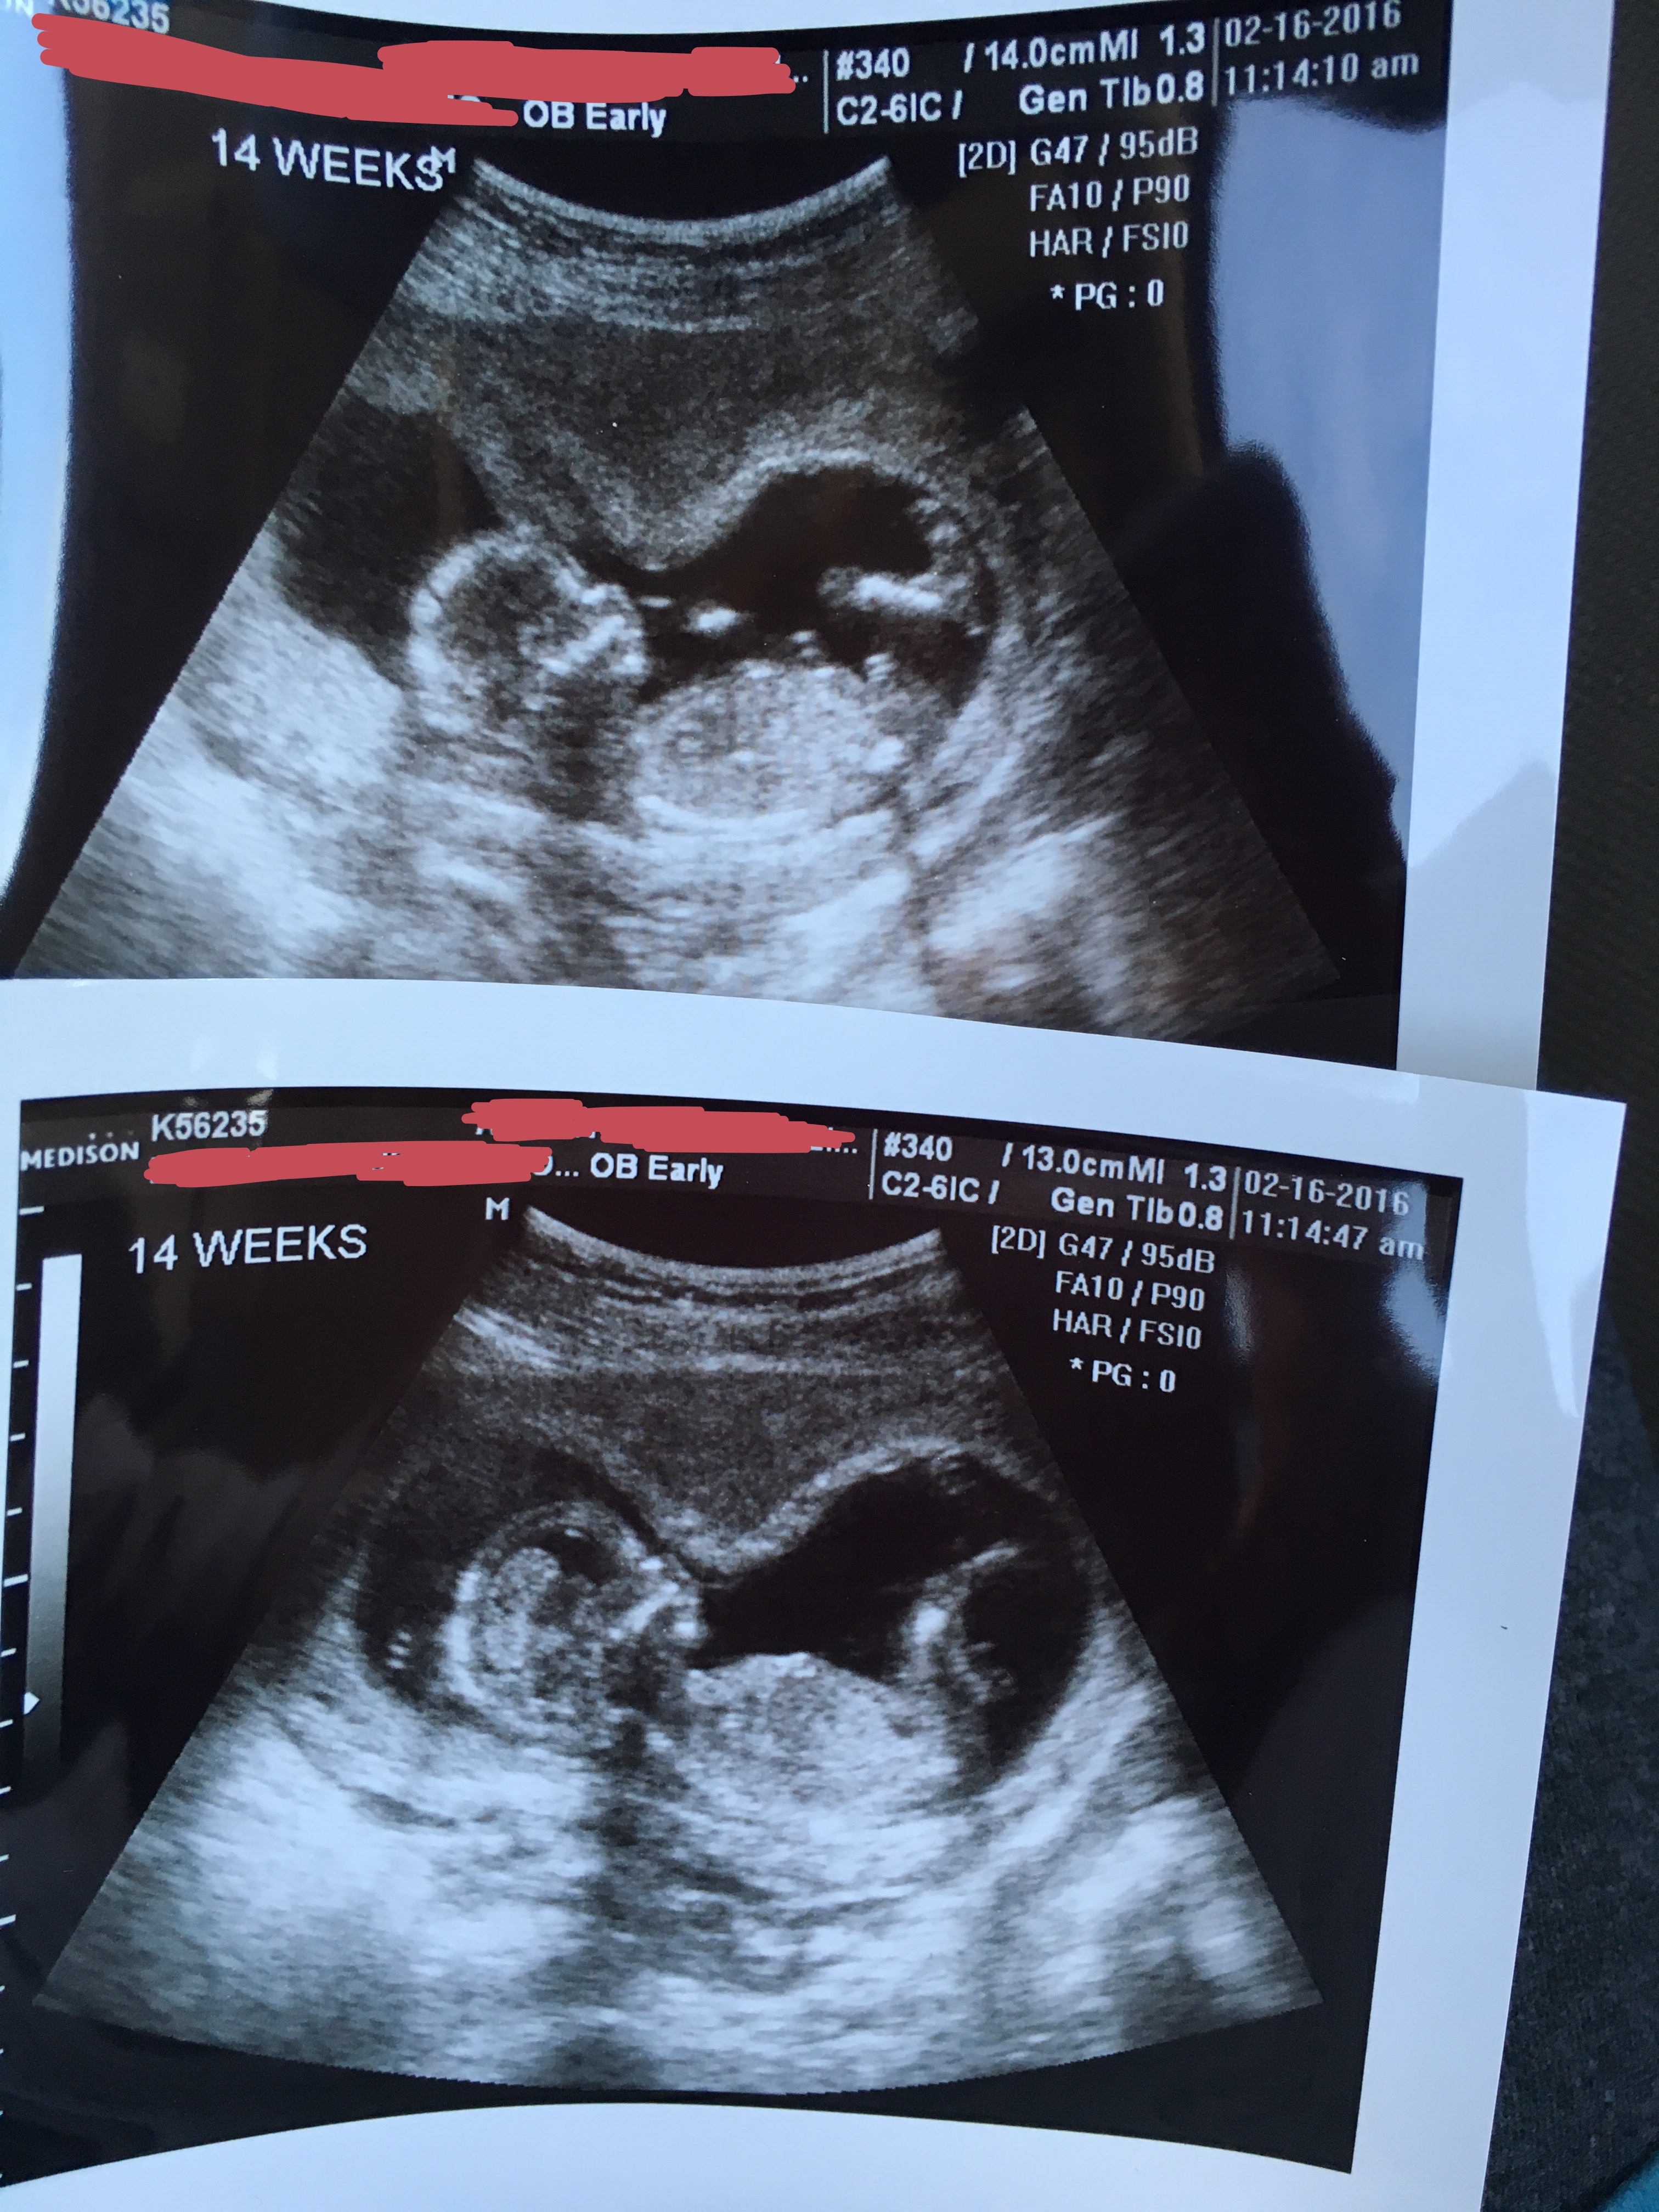

I am 14 weeks! Can you tell whether it's a boy or girl?Attachment 29919

Boy :)

Typical boy nub

Boy!

Yes, looks like a boy! Sent from my SM-N920I using Tapatalk